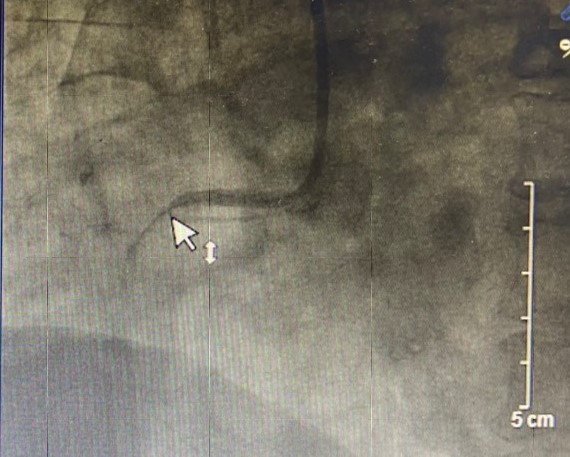

Tại Bệnh viện đa khoa Quốc tế Hải Phòng, bệnh nhân được đánh giá nhồi máu cơ tim có ST chênh lên, block nhĩ thất độ 2. Siêu âm tim phát hiện thất phải hầu như vô động. Ngay lập tức, bệnh nhân được chụp và xét can thiệp cấp cứu, kết quả phát hiện động mạch vành phải của bệnh nhân tắc hoàn toàn do huyết khối nhiều trên nền xơ vữa. Ekip can thiệp: ThS.BSNT Vũ Học Huấn – Trưởng Khoa Tim mạch – Đột quỵ; ThS.BS Phạm Văn Thuận cùng cộng sự đã tiến hành hút huyết khối nhiều lần, lấy ra các cục máu đông đồng thời đặt 1 stent vào vị trí bị tắc. Sau can thiệp ghi nhận dòng chảy tốt, hết huyết khối, huyết động của bệnh nhân đã ổn định, đã cắt vận mạch. Siêu âm tim, thất phải hồi phục tốt, huyết áp người bệnh đã trở lại bình thường. Trong quá trình can thiệp huyết khối nhiều, hình thành nhanh, mặc dù đã được hút huyết khối nhiều lần và đặt stent vị trí hẹp, dòng chảy khôi phục tốt, nhưng các bác sĩ đánh giá nguy cơ huyết khối tái phát cao nên sau can thiệp bệnh nhân được duy trì thuốc kháng tiểu cầu kép kết hợp chống đông đường tiêm nhằm giảm nguy cơ tái tắc mạch do huyết khối.